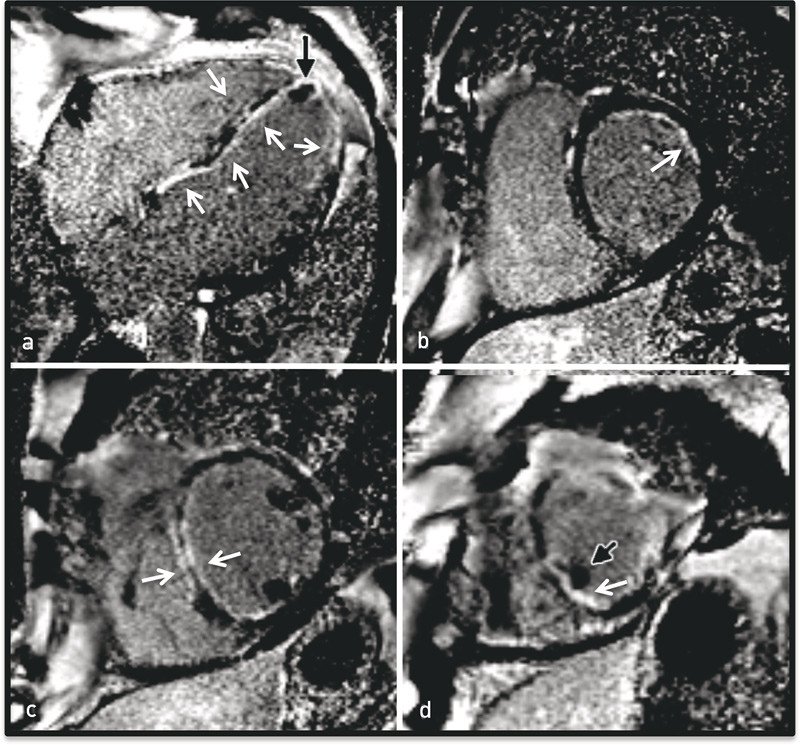

Det ble ikke sett organiserte tromber, men det var betydelig spontankontrast i apikale halvdel av venstre ventrikkel. Det forelå moderat pulmonal hypertensjon (systolisk pulmonalarterietrykk 50 mm Hg, normalt < 30 mm Hg), og det var store regionale forskjeller i veggfortykkelse, uten at dette passet med koronare forsyningsområder (fig 3, video 1).

Bildet var mest forenlig med hjertesvikt med lungestuvning og eventuelt infeksjon. Konsolideringer i underlappene kan være forenlig med eosinofile infiltrater, men er ikke spesifikke for dette. CT av bihulene viste betydelige slimhinnefortykkelser i alle bihuler. MR cor viste dilatert venstre ventrikkel med et endediastolisk volum på 319 ml (normalt 65 – 240 ml) og en ejeksjonsfraksjon på 20 %.

Det ble sett en mindre apikal trombe og omfattende subendokardialt forsinket kontrastopptak etter 10 – 12 minutter som uttrykk for fibrose/nekrose, godt forenlig med iskemi forårsaket av vaskulitt i små kar (e-fig 4, video 2). Dagen etter ble det tatt endomyokardial biopsi. I påvente av biopsisvaret ble det startet, på klinisk, biokjemisk og radiologisk mistanke, behandling for eosinofil granulomatose med polyangiitt.